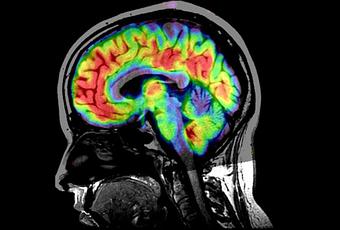

Al final, el efecto fisiológico no es más que una consecuencia que el efecto placebo que tiene sobre el cerebro. La gran mayoría de la información que tenemos sobre los placebos y el cerebro proviene del estudio del dolor. Lo que se ha observado, hasta la fecha, es que el dolor puede ser manipulado para reducirlo con sustancias placebo. Al observar el cerebro con neuroimagen lo que apreciamos es que el efecto placebo tiende a desactivar en parte los centros dedicados a sentir e interpretar el dolor: el tálamo, la corteza somato-sensorial y la ínsula, entre otros. Cuanto más largo es el tratamiento, más se acomodan estas zonas y menos dolor siente el paciente.

Además, el tratamiento con los placebos, según se ha comprobado, también es capaz de disparar una respuesta que viaja a través de la médula espinal, actuando sobre un tejido especial (el tejido gris periacueductal) que produce sustancias naturales que reducen el dolor. Esto último es muy importante y se ha comprobado que bloquear a esta sustancia reduce el efecto placebo por lo que esta sustancia gris periacueductal es un componente principal en el efecto. Otros puntos en el que actúa el efecto placebo son el córtex prefrontal y la amígdala, provocando una mayor regulación de opiáceos naturales en todo el cuerpo. Por otro lado, la amígdala , que controla el estado de ansiedad, por ejemplo, parece muy afectada por el efecto placebo. Estos son solo algunos pequeños ejemplos, porque lo que se observa es que el efecto placebo afecta a cada una de las partes del cerebro con una intensidad inesperada.